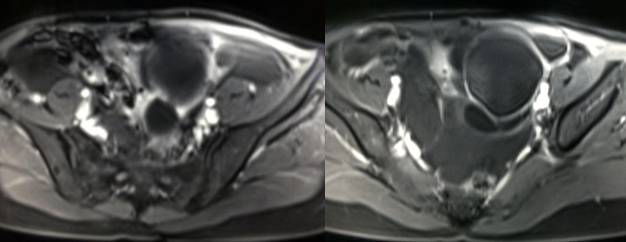

病理结果:黄体血肿

黄体血肿为正常排卵过程中,卵泡层破裂,引起出血,较多的血液潴留在卵泡或黄体腔内形成血肿。

正常黄体直径为15mm左右,以后转变为白体,并在下一个周期的卵泡期自然消退。若黄体内出血量较多,则形成黄体血肿,或称黄体内出血,出血性黄体。黄体血肿多为单侧,一般直径为40mm,偶可达100mm,黄体血肿被吸收后可导致黄体囊肿,较大的血肿破裂时可出现腹腔内出血,剧烈腹痛、少量阴道流血和腹膜刺激征,不易与宫外孕区别。

黄体血肿早期:囊内出血较多时,表现为卵巢内近圆形囊肿,囊壁厚,内壁粗糙。

黄体血肿中期:黄体血肿内血液凝固,部分吸收,囊壁变薄而,内壁光滑。

黄体血肿晚期:血液吸收后囊肿变小,转变为白体,内部回声呈实性稍高回

声,与周围卵巢组织分界不清,面靠彩超显示其周围环状血流判断,当血液完全吸收后形成黄体囊肿,囊壁变得光滑,与卵巢其他囊肿难以区分。

根据时间不同MR信号也有所不同,TIWI脂肪抑制序列可以鉴别脂肪和出血。